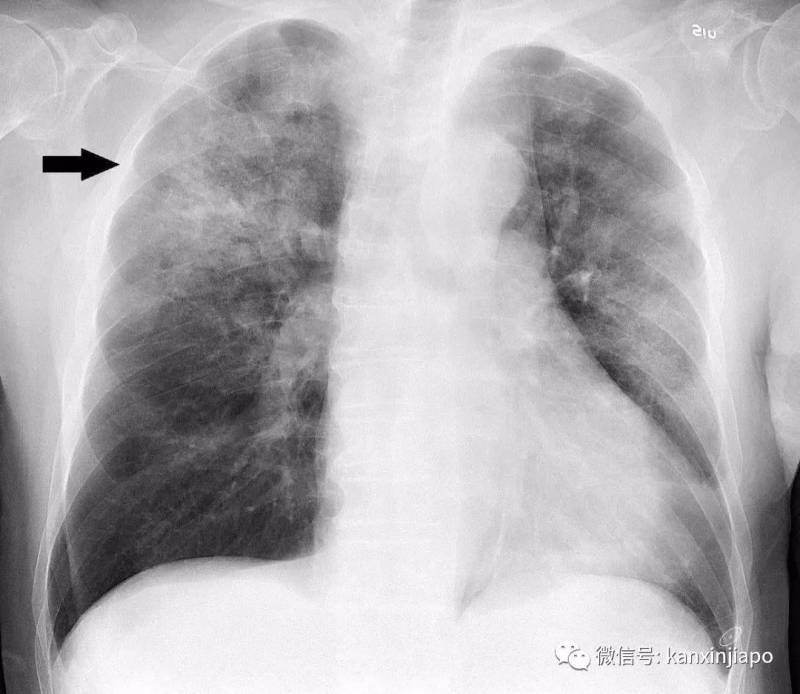

这名26岁的中国籍男子被检查出患有肺炎,而他不久前曾经去过武汉,但并未到访很多人怀疑中的武汉肺炎源头——华南海鲜批发市场。新加坡有关部门现在正调查男子的肺炎是否与武汉肺炎有关,但是作为预防措施,这名男子目前已被隔离、接受进一步的检测及治疗。他目前情况稳定。最近新加坡可是“谈肺炎色变”,1月3日晚上开始,所有从武汉飞往新加坡的旅客,都必须在抵达樟宜机场时接受体温检测。若发现有任何类似于肺炎的可疑病例,将被直接送往医院进行隔离,再做进一步检查。

而在短短一天后的1月4日,新加坡卫生部接到第一起与武汉肺炎疫情有关的可疑病例!当时,一名近期去过武汉的3岁女童被诊断出肺炎。

武汉肺炎“来势汹汹”,截至今年1月5日,武汉市共报告肺炎诊断患者59例,其中重症患者7例。但庆幸的是,到1月8日已经有8名患者出院。这两天,这种不明原因病毒性肺炎的“真凶”已经找到。中国的专家组认为,本次不明原因病毒性肺炎病例的病原体初步判定为新型冠状病毒。